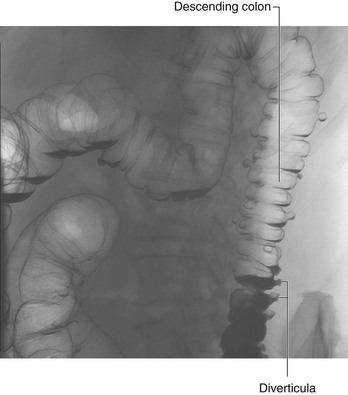

The distal one-third of the transverse colon, descending colon, sigmoid colon, and the superior part of rectum develop from the hindgut.

Proximal parts of the hindgut swing to the left and become the descending colon and sigmoid colon. The descending colon and its dorsal mesentery fuse to the body wall, while the sigmoid colon remains intraperitoneal. The sigmoid colon passes through the pelvic inlet and is continuous with the rectum at the level of vertebra SIII.